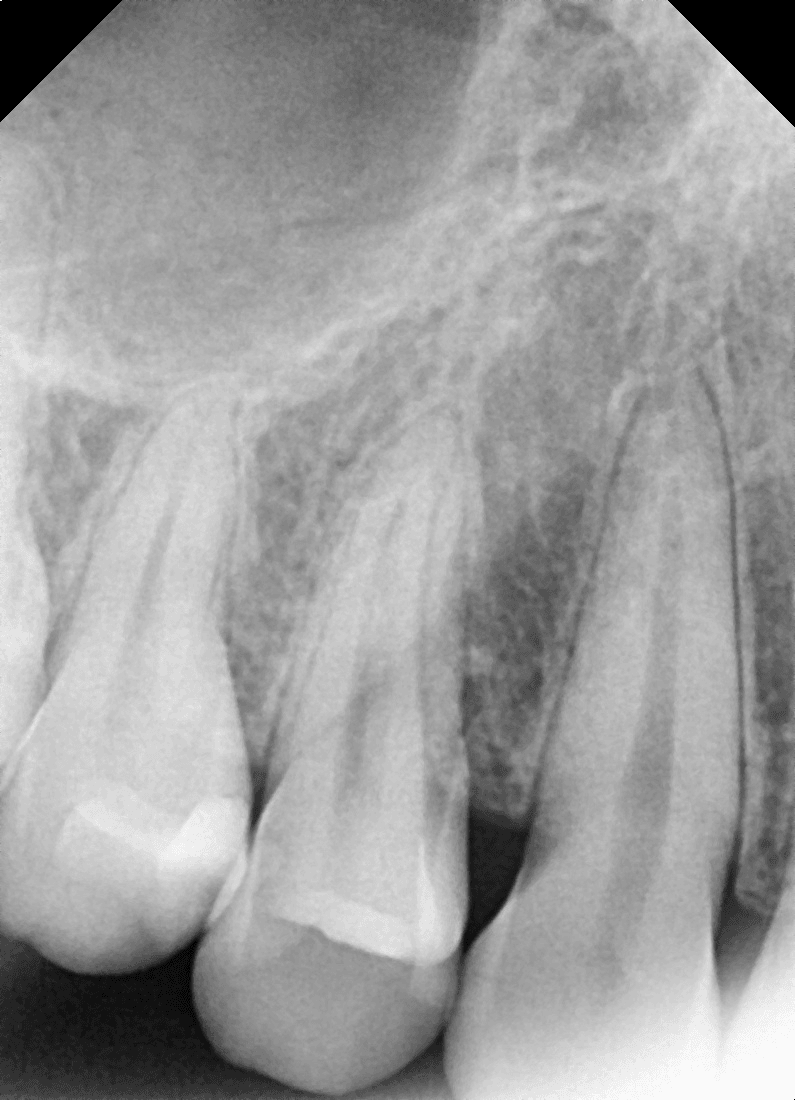

위쪽 어금니에 임플란트를 심었는데, 치아를 올리기까지 얼마나 기다려야 하나요?

상악(위턱)은 하악보다 뼈가 상대적으로 부드럽고, 상악동이라는 구조물이 있어 치유 기간이 더 필요한 경우가 많습니다.

보통 어금니 임플란트를 심은 후 뼈와 임플란트가 단단히 붙는 기간은 약 3~6개월 정도를 예상합니다.

뼈 이식이나 상악동 거상술을 함께 진행한 경우에는 이 기간이 더 길어질 수 있습니다.